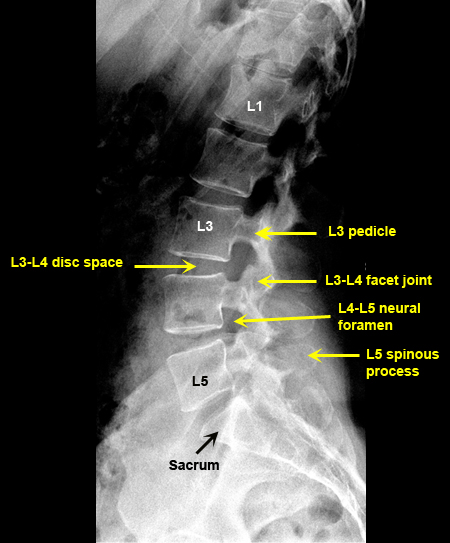

Plain Films of Skull and Spine